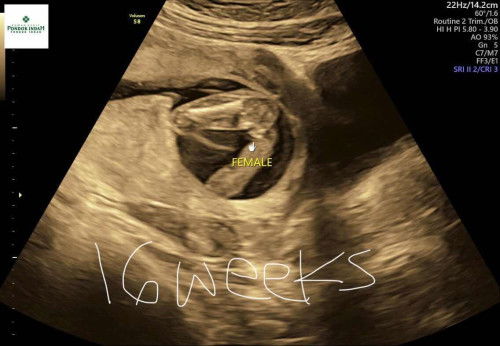

Hasil USG Jenis Kelamin 16weeks

Hallo moms mau tanya dong kalian tau jenis kelamin di usia kehamilan berapa minggu? Bulan lalu aku USG di usia 12weeks dan jenis kelamin sudah terlihat yaitu laki-laki, lalu hari ini USG di usia 16weeks tibatiba jenis kelamin jadi perempuan, memang cek hari ini posisi baby tengkurep dan agak susah diliatnya. Boleh sharing yaa moms, btw ini kehamilan pertamaku mohon doanya yaa moms 🙏🏻 Notes: dibawah ada foto usg ku di 12weeks dan 16weeks